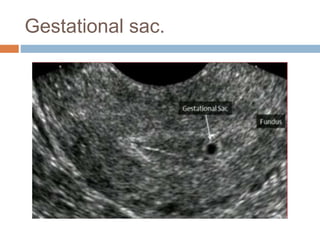

Gestational sac.

 If a gestational sac is seen, its location should

be documented.

 The gestational sac should be evaluated for

the presence or absence of a yolk sac or